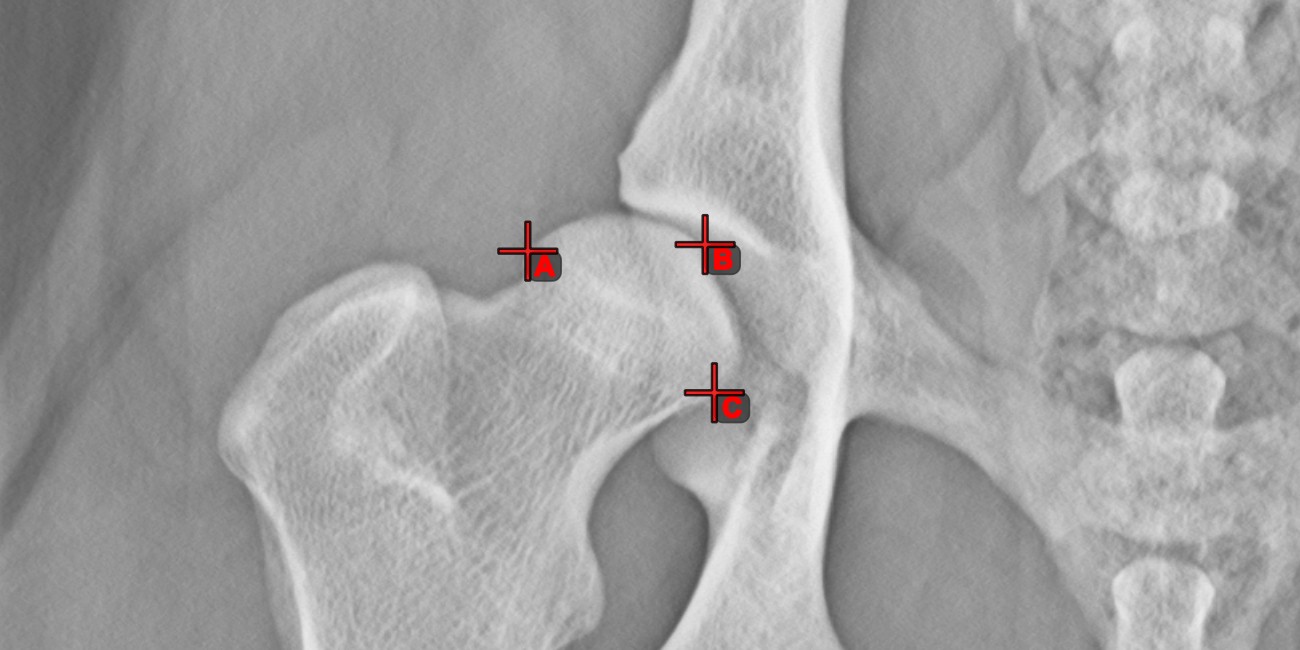

Mark simple points on the image using the Measurement Point tool. Each point is assigned with a letter for better identification.

Modify the position of the points on the image by using the Select/Move Item tool. Select the point by using the assigned mouse button of the tool, and then move it freely anywhere on the image.